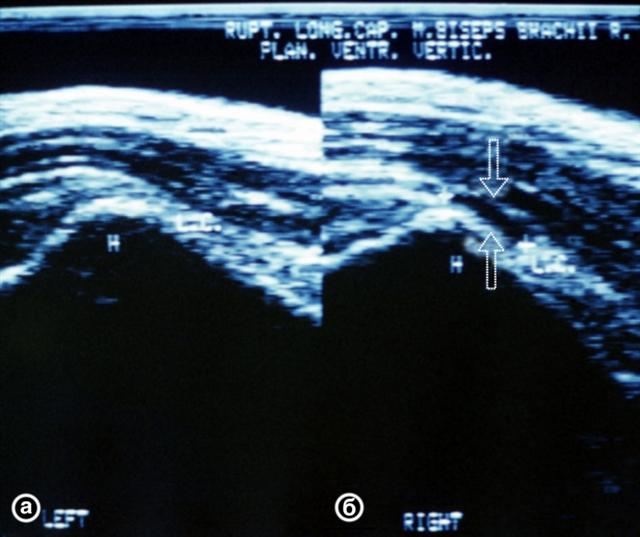

Рис. 3. Ультрасонограмма сухожилия длинной головки двуглавой мышцы плеча в норме (а) и при разрыве (б): зона разрыва указана стрелками.